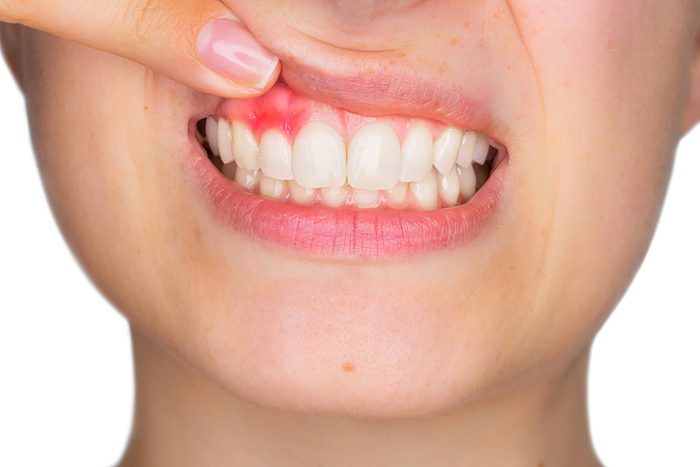

Gum disease

Gum disease, or the infection of the tissues and bones surrounding and supporting the teeth, is caused by poor oral health habits or skipping regular dental visits, which permits the buildup of plaque; risk factors include smoking, diabetes, and certain medications, according to the National Institute of Dental and Craniofacial Research. If you experience signs of periodontal disease—including bad breath, pain when chewing, sensitive teeth, receding gums, loose teeth, tender, red, bleeding, and swollen gums, see your dentist. You can prevent gum disease by using proper oral hygiene. Here are some other reasons why your gums are bleeding.